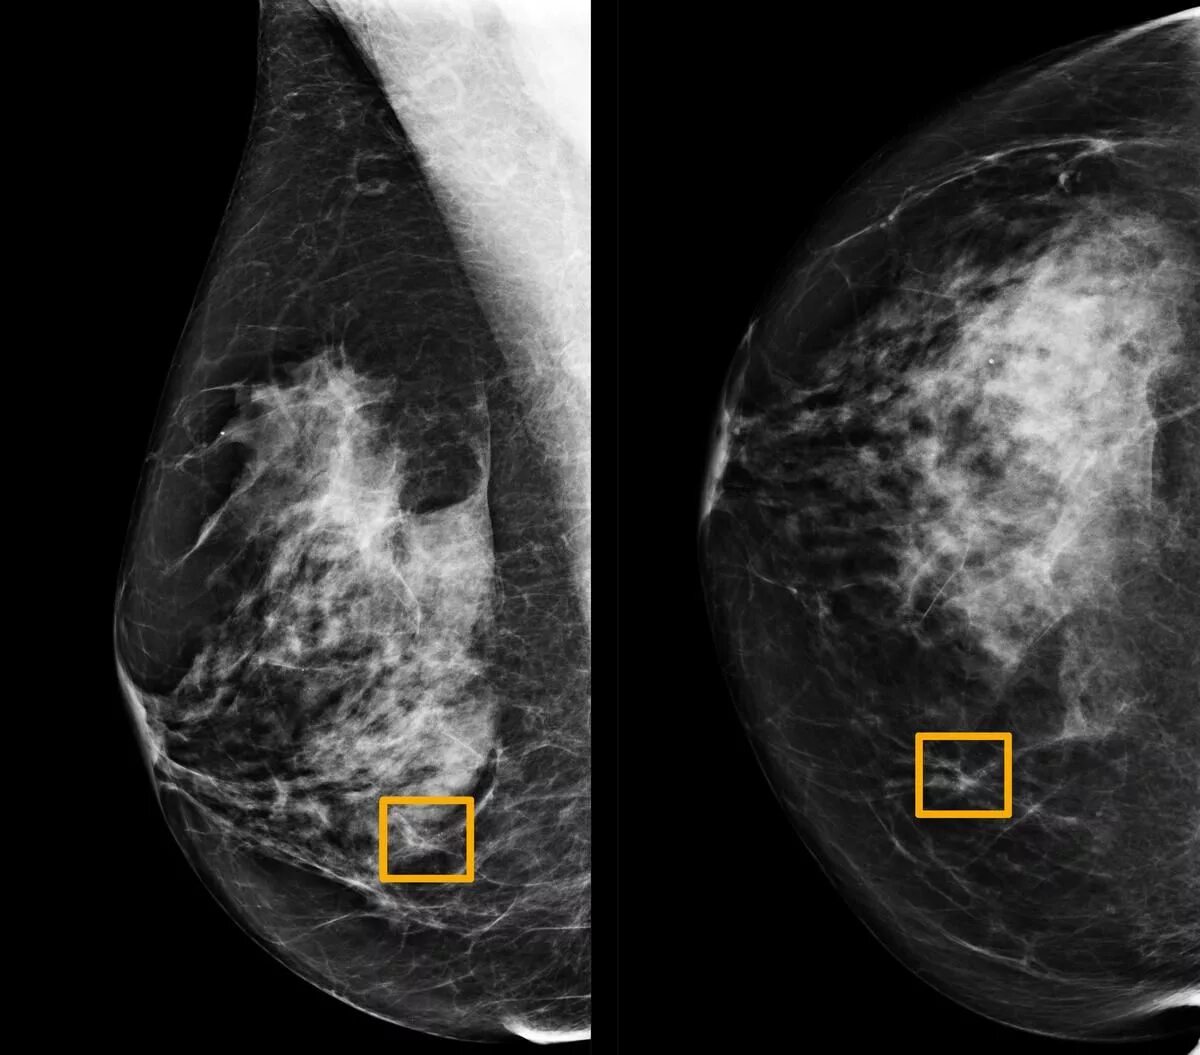

Узловая мастопатия на маммографии. узловая форма мастопатии на маммографии. мастопатия молочной железы на маммографии. маммография снимки норма.

Маммография молочных желез объемное образование. опухоль молочной железы. онкология молочной железы. опухольмолочныйжелезы.

Карцинома молочной железы маммография. опухольмолочныйжелезы. опухоль молочного железа.

Фиброаденома на маммографии. лимфоузлы молочной железы маммография. доброкачественная опухоль фиброаденома. маммограмма доброкачественных опухолей.

Фиброаденоматоз рентген маммография. узловая мастопатия маммограмма. протоковая карцинома молочной железы. болезнь педжета маммография.